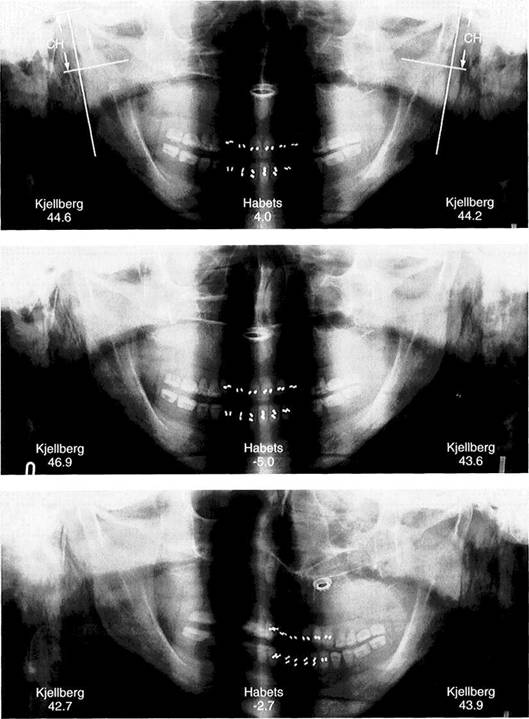

378 Habets, asymmetry index

This asymmetry index (Al) is calculated from the formula Al = [(R-L)/R+L)] x 100% in which R and L stand for the values on the right and left sides. Al can be calculated for either the height of the condyle (CH) or of the ramus (RH). A differ­ence of more than 3% indicates an asymmetrical relationship. Errors can arise, however, through devia­tions in the projection angle or po­sitioning of the patient, and these reduce the reliability of the results (Ferrario et al. 1997, Turp et al.

Kjellberg's asymmetry

index

This determination uses other ref­erence points. By calculaing the quotient of CH:MH or CH:RH in the comparison of the two sides, the magnification error is avoided. The normal values for CH:MH and CH:RH are approximately 35 and 53 respectively. Comparison of the quotients for the two sides allows one to draw a conclusion about asymmetrical relationships in the ascending rami.

CH condyle height

MH         mandible height

RH ramus height

Asymmetry indices for a

patient with hypoplasia of the

right condyle

Comparison of Kjellberg's unilateral index (right and left values with nor­mal values in parentheses) and Ha-bets' asymmetry index (central fig­ures). Even though in this obvious clinical example the values point in the right direction, the clinical sig­nificance of these, and the asym­metry index in general, is very questionable because of the bio­logical variations in condylar form (Ferrario et al. 1997) and length (Turpetal. 1998).

Correct standard positioning

Example of the asymmetry indices of Habets and Kjellberg on the skull of a 67-year-old full denture wearer with increased condylar height on both sides. When the head is cor­rectly positioned in the x-ray unit, the figures for the Kjellberg index are higher than normal, indicating condylar hyperplasia on both sides. Habets' index is likewise elevated and indicates that the right condyle is longer than the left.

382 Distortion from tilting of the head

The same skull tipped 2° to the right. The resulting distortion caus­es the Kjellberg index to indicate that the right condyle is longer than the left. Because of the different reference points used, the curious situation arises that according to Habets' index, there is asymmetry with the greater length on the left side. Because of the short length of CH in Habets' method, small errors in measurement will have a greater influence on the asymmetry index.

383 Distortion from rotation of the head

The same skull turned 10° to the left. The distortion here causes the Kjellberg index to indicate that the left condyle is slightly longer than the right. Habets' index still indi­cates a lengthening on the left side, but within the normal range. To summarize, these experiments demonstrate that Habets' asymme­try index is more subject to errors than that of Kjellberg.